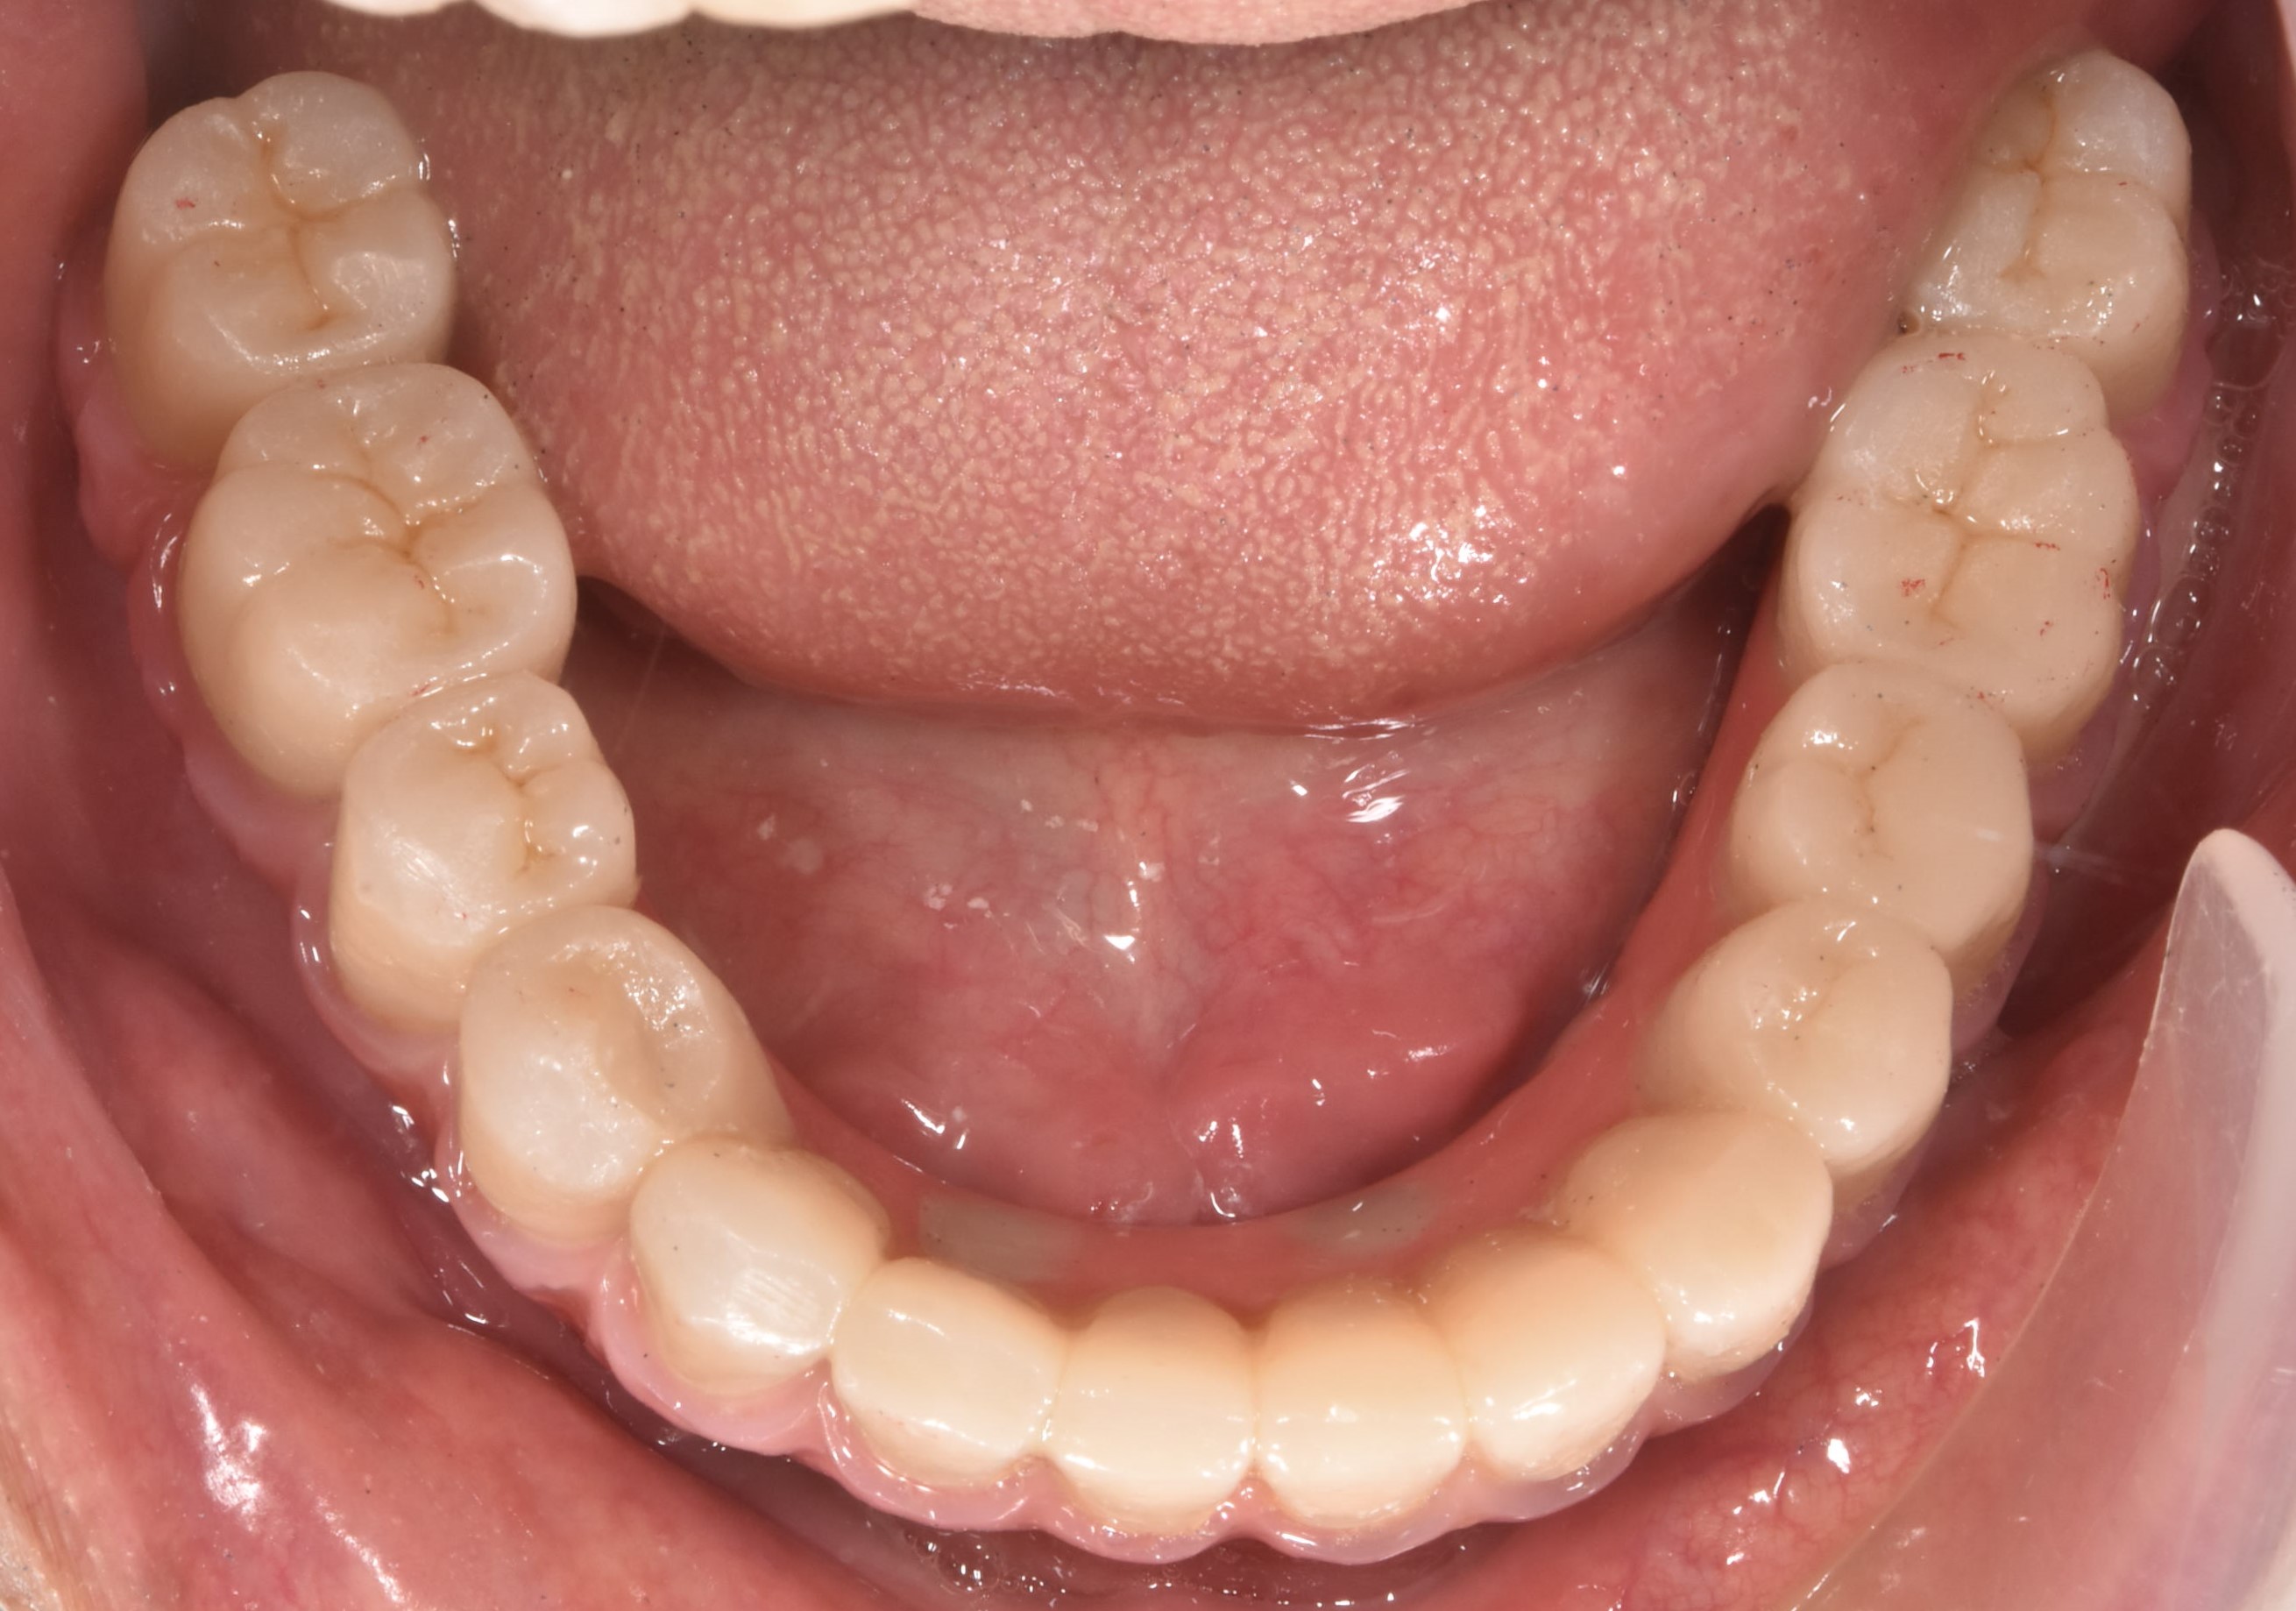

大約3-4的癒合時間,把臨時假牙取下並鎖上正式假牙

完成!